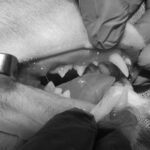

頻繁に嘔吐・下痢をするワンちゃんの精密検査依頼で内視鏡検査のご紹介がありました。内視鏡検査で上部・下部消化管を検査し、粘膜を採取し病理組織検査に出しました。結果は「胃:らせん菌感染を伴う慢性胃炎(中程度)/結腸:慢性腸炎(軽度)」とのことでした。その後かかりつけの先生のところ […]